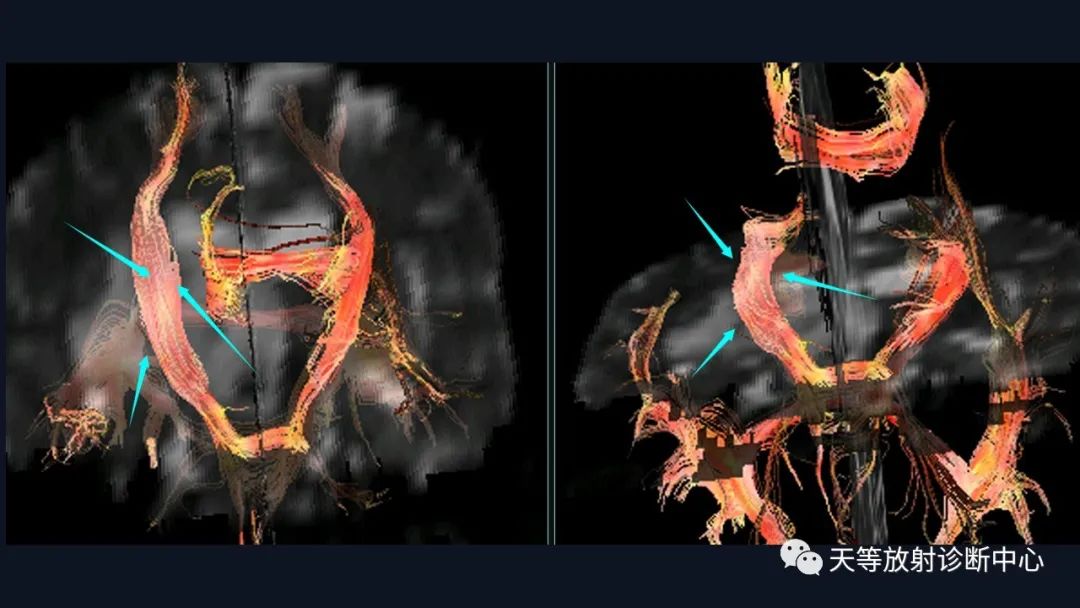

本病例影像学特点:

脑内占位的特点:

1、刀切征

2、凹陷征或肚脐凹征

3、尖角征

4、多发

5、DWI呈稍高信号

6、形态上怪异

6、NAA及Cho减低,出现导致LL峰。

结合颈部、胸廓入口区及腋窝多发淋巴结肿大并相互融合。

综合考虑淋巴瘤